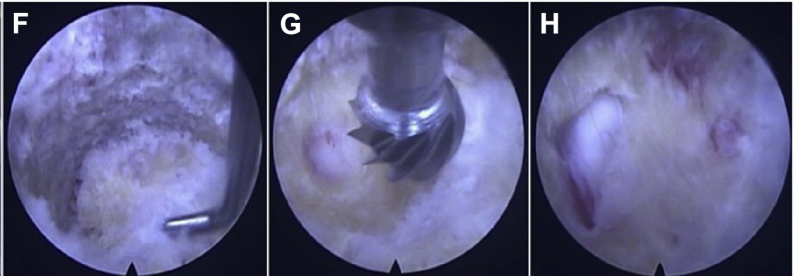

F.钝钩确认后纵韧带;G.磨钻将后纵韧带打磨出裂孔,如网格状;H。减压后可见硬膜膨隆

6.硬膜和韧带骨化之间的粘连使用钝钩分离,而剩余的骨膜病变则使用沿脊髓表面用咬骨钳去除,看到硬膜囊再次扩张,则为彻底减压。